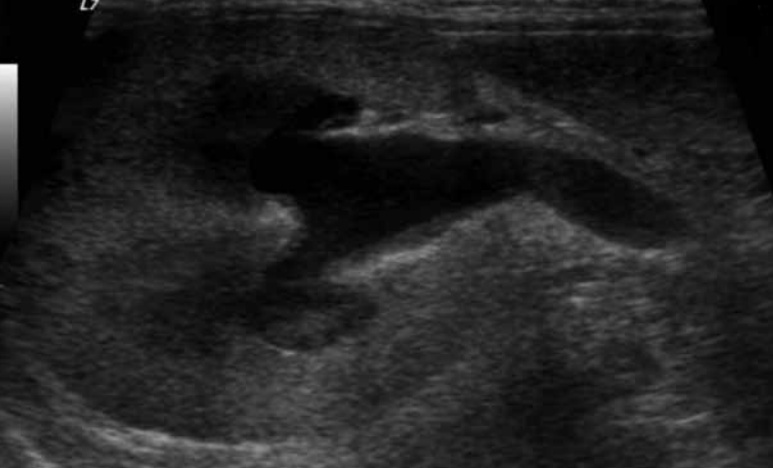

6-1. 수신증(Hydronephrosis)(그림 12)

수신증은 신우 확장 및 신배(diverticula) 확장을 의미하며, 3mm 이상 확장은 비정상으로 간주됩니다.

대부분 근위 요관의 확장(hydroureter)이 동반되며, 원인으로는 만성 감염(신우신염, 요관염), 신장 원위부 요로 폐색을 일으킬 수 있는 방광 삼각부 종양, 요관 결석, 요관 종양, 외상 또는 만성 요관염에 의한 협착, 신결석, 신우 종양 그리고 이소성 요관 등이 있습니다. 고양이에서는 요관 결석에 의한 폐색이 가장 흔한 원인으로 알려져 있습니다.

초음파 영상의 특징으로는 신장 비대, 윤곽은 대체로 매끄러우나 무에코 액체가 신우에 축적되고 원위부에 음향 증강이 있습니다. 확장 정도는 경미~중증까지 다양하며, 진행 시에는 신실질 압박이 피질을 위축시키고 신배 확장을 보입니다. 심하면 격벽성 낭성 구조를 보이며, 완전 폐색 시에는 확장된 신우 주변에 얇은 피질 띠만 남게 됩니다.